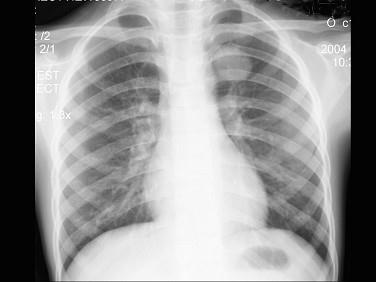

问题 患者男性,9岁,常年咳嗽,无其他自觉症状,X线检查如图所示,最可能的诊断是 ( )

选项 A、纵隔肿瘤 B、原发性肺癌 C、炎性假瘤 D、结核球

答案 C